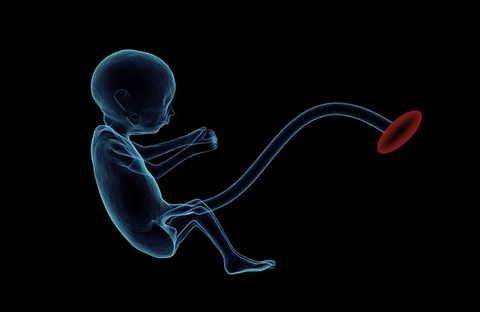

プラセンタとは、哺乳動物の胎盤のことで、胎児の生命を維持し、

成長を促す大切な働きを担っています。ですから、

生体に働きかける多彩な作用が期待できるのです。